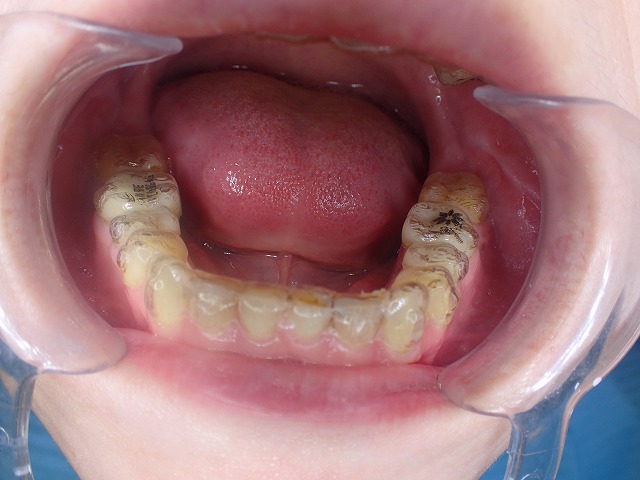

まずは下顎から診査

インビサラインのマウスピースが入っています。

この状態で奥歯をジルコニアに交換するのは

難題です。

かぶせ物を交換した場合には

この維持装置が使えなくなる場合があるので

維持装置を作り直す必要の可能性があります。